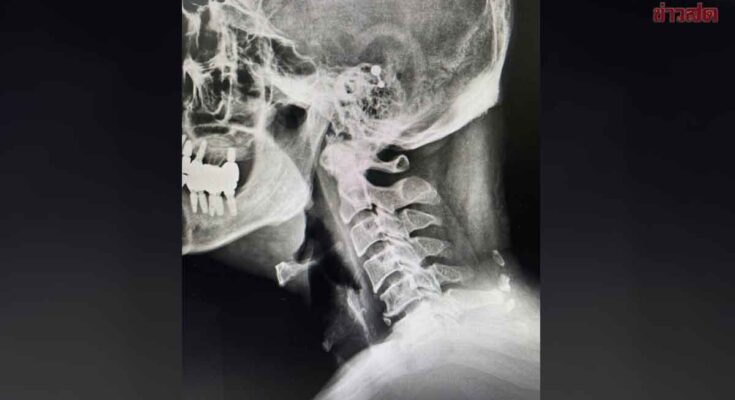

ผศ.นพ.ธนินนิตย์ ลีรพันธ์ แพทย์ผู้เชี่ยวชาญกระดูกและข้อ โพสต์ข้อความบนเพจเฟซบุ๊ก ‘หมอเก่งกระดูกและข้อ’ ระบุว่า ถ้ากระดูกคอเสื่อมแล้ว จะกลับมาดีเหมือนเดิมได้ไหม?

กระดูกคอเสื่อม = ไม่หายขาด แต่ดีขึ้นได้ ความจริงก็คือกระดูกที่เสื่อมแล้วจะไม่กลับมาเหมือนตอนอายุ 20–30 ปี ได้ 100% เพราะการเสื่อมเป็นส่วนหนึ่งของวัยและการใช้งาน